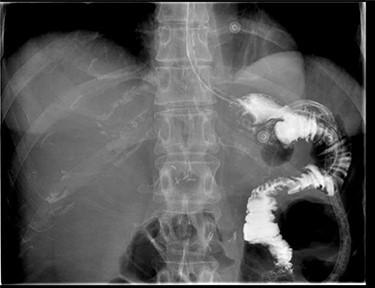

Macroscopically there was no suggestion of malignancy or mass lesions; instead, it was felt that the fistula was likely caused by the advanced ulceration previously demonstrated on gastroscopy. The patient was commenced on total parenteral nutrition to optimize her nutrition preoperatively, and then 1 week after admission was taken to the operating theatre for definitive surgical management. At laparotomy, an inflammatory mass involving the distal stomach, transverse colon and Roux limb of the previous Roux-en-Y reconstruction was found. An uncomplicated near completion gastrectomy and segmental colectomy was performed, with the partially resected Roux limb able to be mobilized sufficiently to allow for the near-total gastrectomy to be appropriately reconstructed to the alimentary canal. Histopathology of the resected tissue was consistent with chronic inflammation and ulceration, with no evidence of malignancy. The patient recovered well post-operatively and a gastrograffin meal did not show any suggestion of ongoing fistulous communication or anastomotic leak (Fig. 3). She was discharged home Day 12 post-operatively on high-dose pantoprazole, and has since made an excellent recovery with resolution of her symptoms and improved nutritional status.

Gastrografin meal at 7 days post-operatively demonstrating resolution of gastrocolonic fistula.